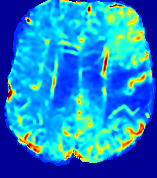

LesionRefer to captionRefer to captionRefer to captionRefer to captionRefer to captionRefer to caption𝐕rgbsubscript𝐕𝑟𝑔𝑏{\bf{V}}_{rgb}Refer to captionRefer to captionRefer to captionRefer to captionRefer to captionRefer to caption𝐕2subscriptnorm𝐕2{\|\bf{V}}\|_{2}Refer to captionRefer to captionRefer to captionRefer to captionRefer to captionRefer to captionRefer to caption3.53.53.52.82.82.82.12.12.11.41.41.40.70.70.70.00.00.0(mm/s)𝑚𝑚𝑠(mm/s)D𝐷DRefer to captionRefer to captionRefer to captionRefer to captionRefer to captionRefer to captionRefer to caption0.0200.0200.0200.0160.0160.0160.0120.0120.0120.0080.0080.0080.0040.0040.0040.0000.0000.000(mm2/s)𝑚superscript𝑚2𝑠(mm^{2}/s)Slice #1Slice #2Slice #3Slice #4Slice #5Slice #6

Figure 3: PIANO feature maps for one stroke patient, where the lesion is located in the left hemisphere. Top row: segmented stroke lesion region (white) on different slices, obtained from ISLES 2017. The corresponding slices for the PIANO feature maps are shown in the following rows.

For a better insight into an estimated velocity field 𝐕𝐕{\bf{V}} and diffusion field 𝐃𝐃{\bf{D}}, we compute the following maps: (1) 𝐕rgbsubscript𝐕𝑟𝑔𝑏{\bf{V}}_{rgb}: Color-coded orientation map of 𝐕=(Vx,Vy,Vz)T𝐕superscriptsuperscript𝑉𝑥superscript𝑉𝑦superscript𝑉𝑧𝑇{\bf{V}}=(V^{x},V^{y},V^{z})^{T}, obtained by normalizing 𝐕𝐕{\bf{V}} to unit length and mapping its 3 components to red, green, blue respectively; (2) 𝐕2subscriptnorm𝐕2\|{\bf{V}}\|_{2}: 222 norm of 𝐕𝐕{\bf{V}}; (3) D𝐷D: scalar field in Eq. 5.

Fig. 3 and Fig. 4 show the PIANO feature maps estimated from two ISLES 2017 patients: all are highly consistent with the lesion in both cases. Details of the blood flow trajectories are revealed in 𝐕rgbsubscript𝐕𝑟𝑔𝑏{\bf{V}}_{rgb} by the ridged patterns and the sharp changes of colors in the unaffected (right) hemisphere, while the flat patterns appearing within the lesion provide little directional information about the velocity and indicate low velocity magnitudes. Velocity magnitudes are more directly visualized via 𝐕2subscriptnorm𝐕2\|{\bf{V}}\|_{2}, from which one can easily locate the lesion where 𝐕2subscriptnorm𝐕2\|{\bf{V}}\|_{2} is low. D𝐷D also indicates lower diffusion values in the lesion, though with less contrast potentially due to the fact that it captures the accumulated effect of CA diffusion at the voxel-level.